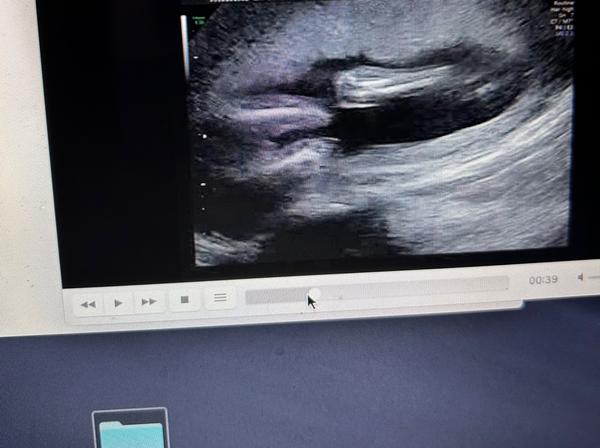

chtěla bych se zeptat na pohlaví miminka. 🙂

z fotografií nelze jednoznačně říci. ☹ Výpovědní hodnotu vyšetření "naživo" fotografie nedokáží nahradit.